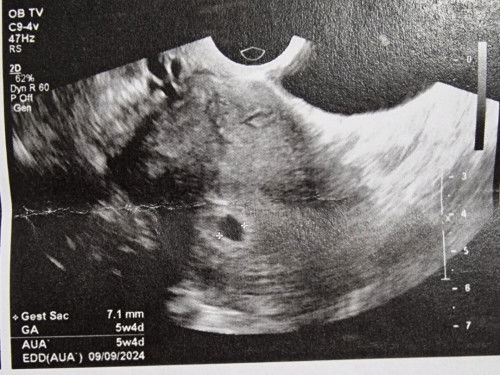

Gestational sac only

Hi all according to my LMP, I am exactly 7 weeks today and I got my 1st vaginal scan. However, there was only a 7mm gestational sac and ultrasound says its 5w4d. I've only had bloating and felt extreme fatigue with a little cramps once in awhile. No nausea/vomiting. Dr asked me to return for a rescan in 1 to 2weeks time. I'm very worried now cos mine is a 28day cycle mostly. Any advice? Do I go back for a scan in 1 week time or should I wait for 2 weeks?#pleasehelp #firsttimemom #advicepls